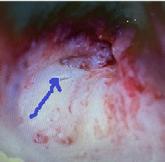

O femeie de 79 de ani COVID+ s-a deplasat la secția de Oftalmologie cu colecție fistulizată în treimea interioară a polului anterior a pleoapei inferioare. Inițierea tratamentul s-a efectuat cu Cefort 1 gr și Gentamicină 80 mg și antiinflamatoare. Examenul CT a evidențiat formarea chistică cu dimensiunile de 2,7/1,5 cm adiacent cantului medial al ochiului stâng cu extensie la nivelul canalului naso-lacrimal cu un calibru crescut. Datorită evoluției staționare s-a cerut consult în serviciul de Otorinolaringologie.

O femeie de 79 de ani s-a internat de urgență în Secția de Oftalmologie cu infecție SARS-CoV-2 pozitivă acuzând: edem periorbitar, cu motilitate oculară păstrată, fără diplopie, fără exoftalmie, fără chemozis, secreții purulente în sacul conjunctival, cornee transparentă, pupila rotundă centrală, iris cu model radial, cataractă corticonucleară, canale lacrimale nepermeabile. Abcesul a fistulizat exterior în treimea interioară a polului anterior al pleoapei inferioare asociind hiperemie și

edem palpebral. Antecedentele heredocolaterale evidențiază un istoric de hipertensiune arterială și un cancer mamar operat radiotratat, care nu a fost relevant pentru strategia de tratament. Se inițiază un tratament antibiotic intravenos cu: Ceftriaxona 1 gr la 12 ore asociat cu Gentamicină 80mg/2ml la 12 ore, tratamentul local a fost asocierea de: Bethametazona și soluție Cloramfenicol (Betabioptal). După 24 de ore de tratament edemul pleoapei este remis dar rămâne un edem eritematos, indurat inferior (din unghiul intern spre treimea externă), fără chemozis, nedureros, mobilitate prezentă, fără diplopie în toate cadranele, restul polului de aspect normal. Pacienta a avut o stare generală bună, afebrilă, fără tulburări de motilitate vizuală și oculară. Nu au fost raportate antecedente traumatisme faciale. S-a efectuat un examen CT cerebral în urma căruia s-a evidențiat o formațiune chistică cu dimensiunile de 2,7/1,5 cm adiacent cantului medial al ochiului stâng cu extensie la nivelul canalului naso-lacrimal arătând un calibru crescut cu o densificare difuză asemănătoare celulitei a țesutului palpebral stâng și cu osteoliză la nivelul laminei papiracee. Pacienta a refuzat tratamentul SARSCoV-2 și, din cauza progresului staționar, a fost trimisă la secția de Otorinolaringologie pentru a doua opinie. Inițial s-a verificat permeabilitatea ductului naso-lacrimal, s-a schimbat tratamentul cu antibiotice Ceftriaxona cu Levofloxacina, s-a practicat o incizie la nivelul orificiului

de fistulizare pentru un drenaj eficient al abcesului urmat de tratament local. Evoluția pacientei a fost favorabilă astfel încât după 4 săptămâni s-a efectuat intervenția endoscopică de dacriocistorinostomie (DCR) pentru evaluarea permeabilității ductului naso-lacrimal. Evoluția după 2 luni de la operație nu a evidențiat recidiva abcesului iar permeabilitatea ductului a fost restabilită.